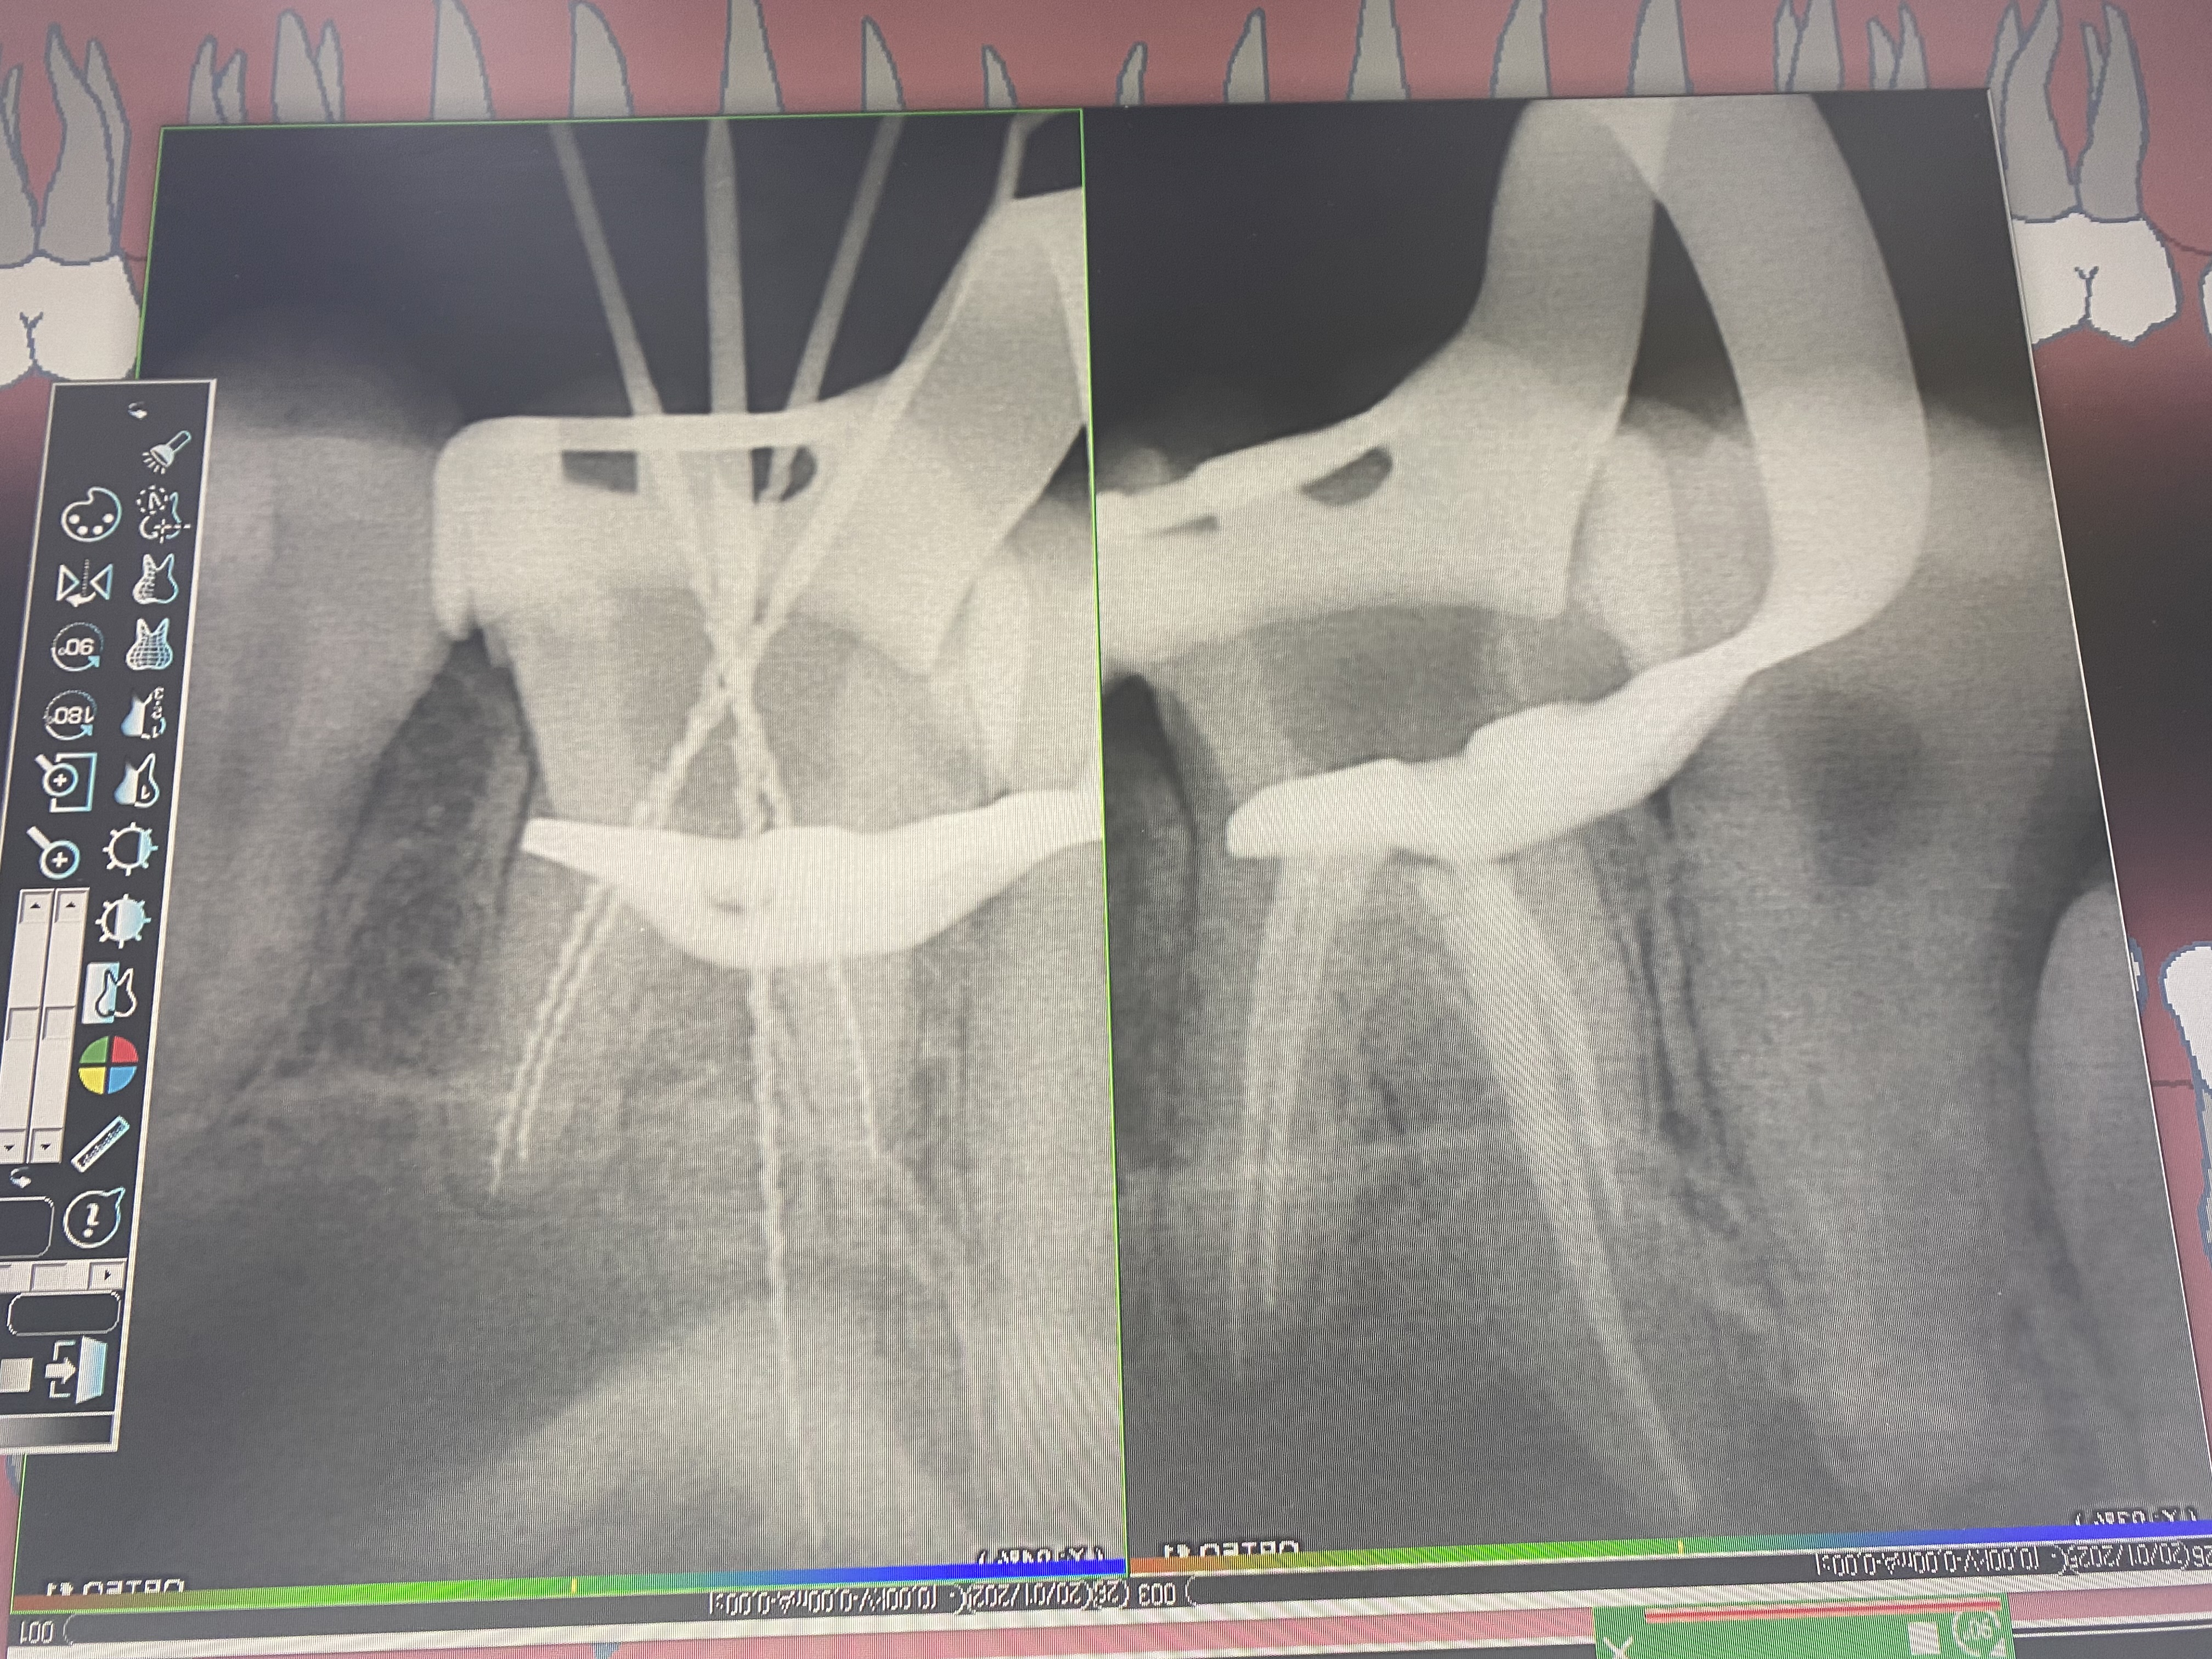

- Проведение полной профессиональной консультации по здоровью зубочелюстной системы, составление комплексного плана лечения, рекомендации по поддержанию качественной гигиены полости рта, обучение правильной технике чистки зубов, анализ снимков на визиографе и рентген-аппарате, анализ Клкт снимков

- Владение современными методиками пломбирования корневых каналов, обработки и распломбировки многокорневых зубов любой степени сложности